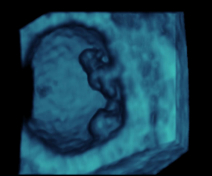

Desarrollo del feto

Cómo crece el bebé dentro de ti

Semana a semana descubrirás cómo se produce el desarrollo fetal. Sabrás cómo crece tu hijo dentro de ti, cuánto mide y pesa, cómo se desarrollan sus órganos, sentidos, qué experimenta… Además encontrarás consejos para aliviar las molestias que experimentas y claves para alimentarte mejor, según la semana de gestación en la que te encuentras.